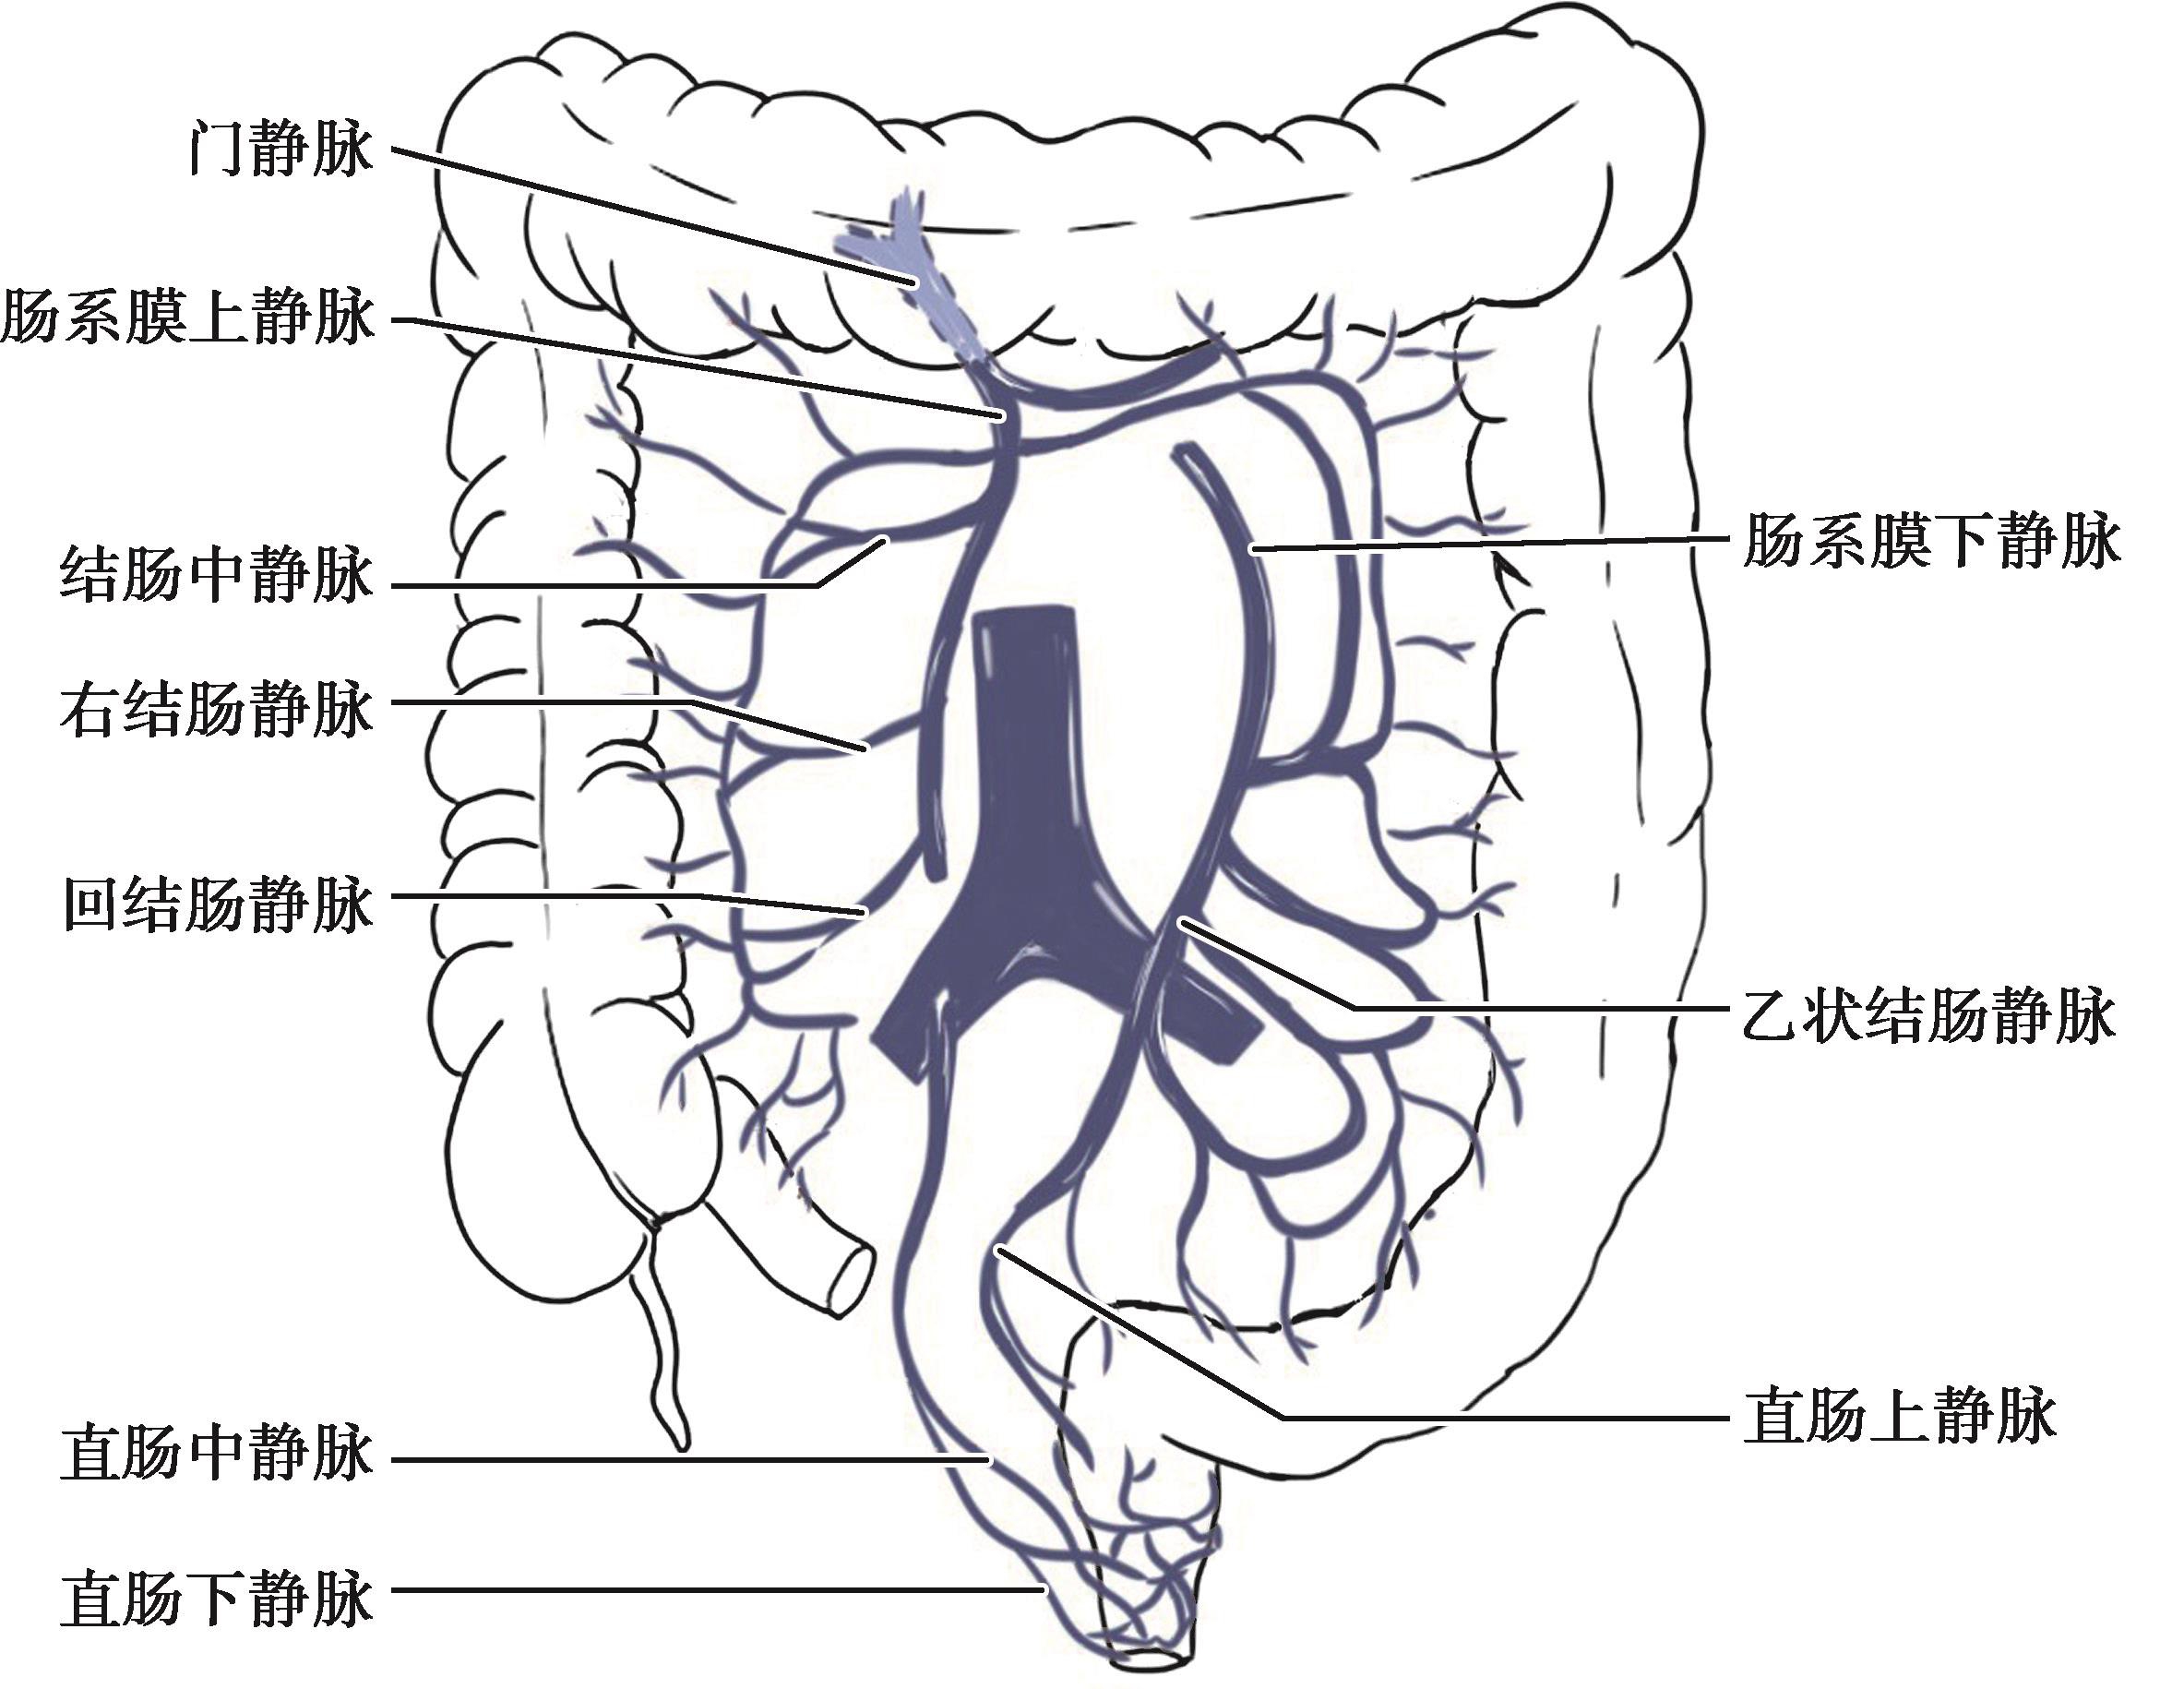

图2-7 结肠静脉回流

各段结肠静脉均与动脉伴行;左半结肠的静脉(直肠、乙状结肠、降结肠)汇入肠系膜下静脉经肠系膜上静脉或脾静脉,最后回流到门静脉;右半结肠的静脉(回结肠、阑尾、盲肠、升结肠、横结肠)则经肠系膜上静脉直接回流到门静脉。